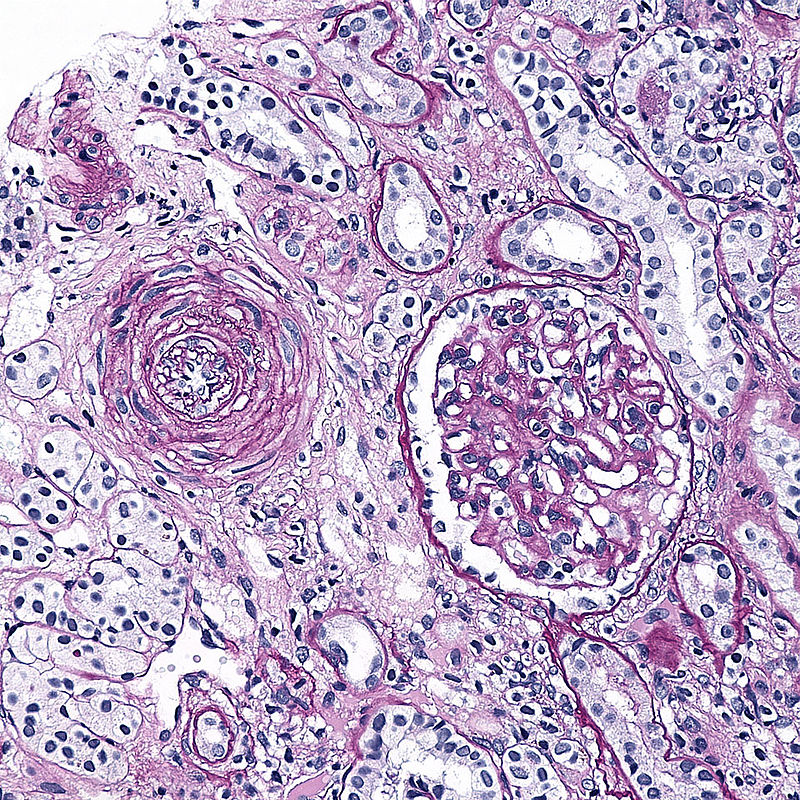

Arteriolosclerosis is categorized as hyaline and hyperplastic varieties.

Protein leakage into the arterial wall, which results in vascular thickening, is the primary cause of hyaline arteriolosclerosis.

On microscopy arteriosclerosis appears as pink hyaline around the circumference of the vessel.

Hyperplastic arteriolosclerosis thickens the artery wall by causing smooth muscle hyperplasia in an “onion-skin” pattern.

Fibrinoid necrosis of the vessel wall may also be seen in hyperplastic arteriolosclerosis.

Malignant hypertension may be related to hyperplastic arteriosclerosis due to rapid decreased vessel diameter.